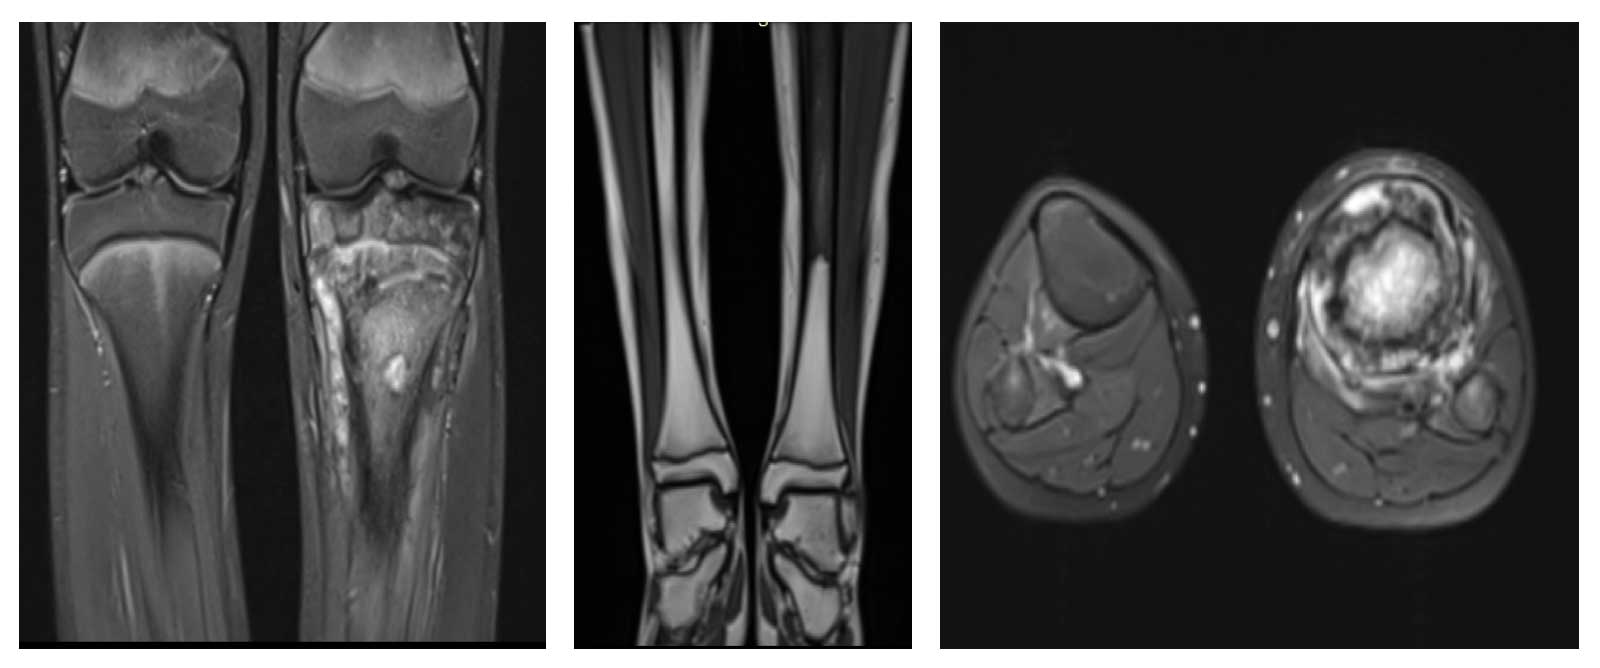

Ameliyat Öncesi: MR’da proksimal tibiada kemik harabiyetine neden olup yumuşak dokuya uzanım gösteren çevreleyen ödemin eşlik ettiği düzensiz sınırlı kitle lezyonu.